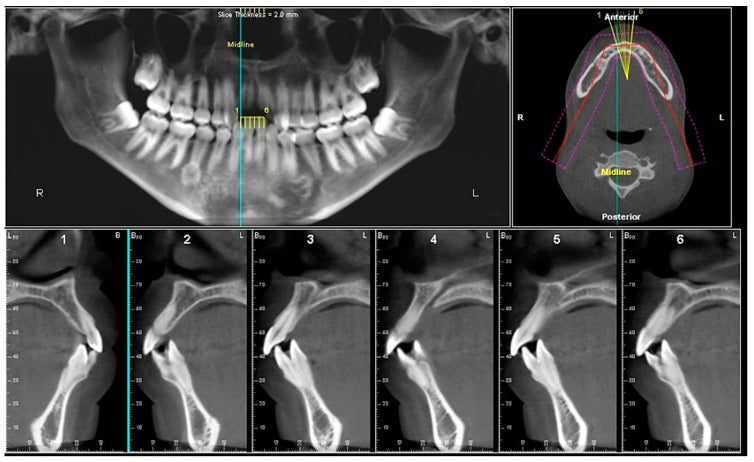

Cone Beam Computed Tomography (CBCT) is also known as C-arm CT, cone beam volume CT, flat panel CT, Digital Volume Tomography (DVT), or Digital Volume CT. South Korea Cone-Beam Computed Tomography (CBCT) Systems Market is predicted to reach USD 92 million with a CAGR of 16% by 2030, according to industry analysts at Next Move Strategy Consulting.

Strong Adoption in Dentistry: Similar to other advanced economies, the dental sector is the primary driver of CBCT system adoption in South Korea. CBCT systems are essential in dental imaging for accurate 3D imaging, implant planning, and orthodontic treatment, making them a staple in dental clinics and hospitals across the country.

Technological Advancements in CBCT Systems: South Korea is known for its rapid adoption of cutting-edge technology, and CBCT systems are no exception. Innovations in the CBCT space, such as portable models, reduced radiation exposure, and improved image quality, are fueling demand in both the medical and dental sectors. These advancements make CBCT a preferred choice for healthcare providers in South Korea.